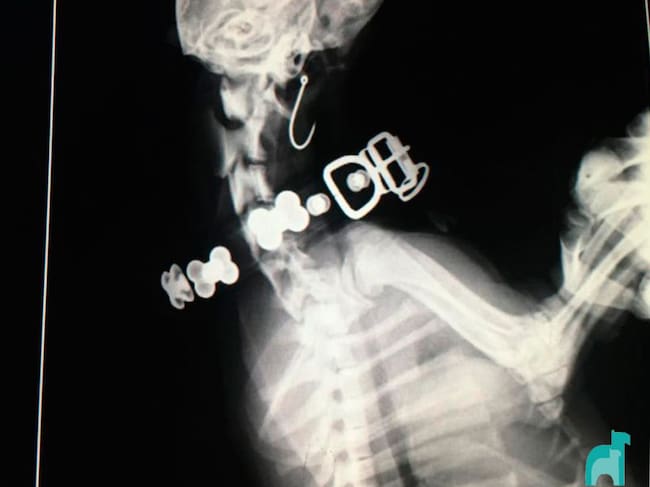

Radiografía de Zoe donde se el anzuelo ingerido. / Hospital Veterinario Asturias

La historia tiene final feliz. Los hechos sucedieron el martes de Carnaval en torno a las ocho de la tarde. Zoe paseaba junto a su dueña por los alrededores de la escalera dos, cuando se encontró un anzuelo abandonado y se lo tragó. Marta González acudió de manera inmediata a una clínica veterinaria donde le sometieron a "una apertura lateral en la garganta, para posteriormente cortar el hilo por la mitad y sacar ambos trozos", han explicado desde la clínica. La operación costó unos 350 euros.